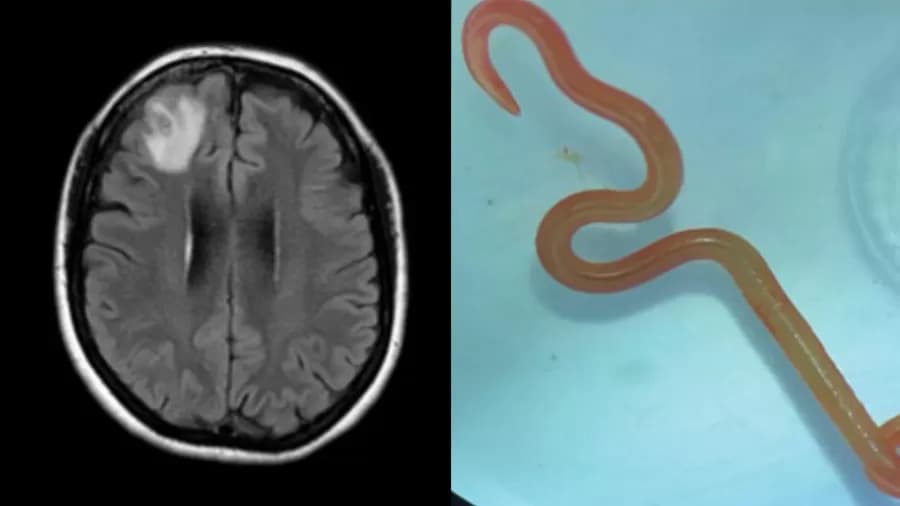

À esquerda, a imagem da ressonância feita no cérebro da paciente; À direita, o verme retirado do órgão (Foto: Divulgação/Emerging Infectious Diseases)

Um caso curioso e assustador foi publicado na revista médica Emerging Infectious Diseases: Um verme de 8 cm foi retirado do cérebro de uma mulher de 64 anos, na Austrália.

Sem encontrar uma explicação para os sintomas dela, os médicos efetuaram uma ressonância e uma biopsia. Foi quando constataram a presença do verme, que estava provocando anormalidades cerebrais na mulher.

Ela passou por cirurgia e o verme foi retirado. Após a operação, pesquisas constataram que o verme era da espécie Ophidascaris robertsi, comumente encontrada em pítons. Os cientistas acreditam que a mulher foi infectada ao tocar vegetação onde o parasita foi depositado em fezes das cobras.